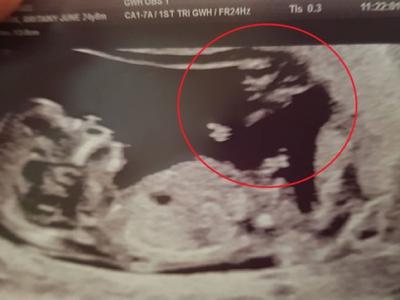

英国不易受孕年轻夫妻奇迹怀孕 超音波照

英国不易受孕年轻夫妻奇迹怀孕 超音波照惊见“天使”守护神(神秘的地球uux.cn报道...